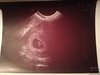

Gratulacje! Czyli jednak jedno. Serduszko ale. Jak. Ważne [emoji8] [emoji173] [emoji7]Dziękuję dziewczyny za wszystkie miłe słowa [emoji173]️

A to nasz mały skarb [emoji173]️[emoji173]️Zobacz załącznik 850648